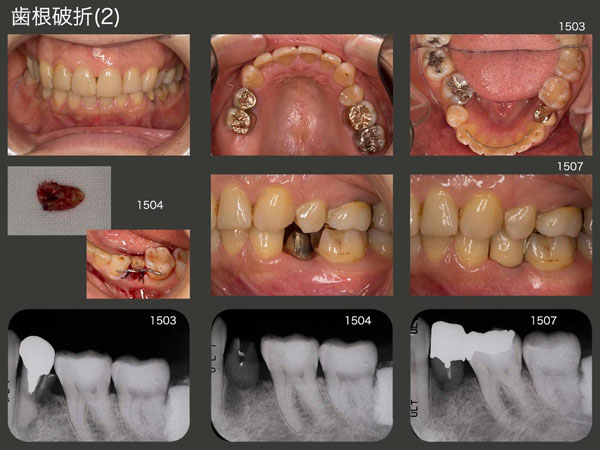

4.歯根破折(2)

2015年3月初診,55歳の女性.左下4の咬合時痛を訴えて来院.デンタルX線写真から歯根破折がみられた.右側は,右上7が欠損,右下6が舌側に転位しているため,右側では咬みにくく,どうしても左側咬みになってしまう.この結果,無髄歯である左下4の歯根破折が生じたと考えられる.なお,この患者さんは最近歯科矯正を行っており,前歯は綺麗に並んだが,その代償として右下6が舌側に転位してしまったという経緯がある.

破折は根尖側から3分の1にまで達していたが,何とか保存したいと考え,再植を行った.なお,再植にあたっては,破折のある遠心面を90度回転し,頰側に位置づけた.さすがに単独植立は無理なので,左下6のコンポジットレジンを除去し,左下4および6の連結冠・インレーを装着した.単純に抜歯し,ブリッジとすれば,バージントゥースである左下3を削る必要が生じるが,再植によって回避することができた.

患者さんには,嚙みにくいけど,右側でも嚙むように指導している.